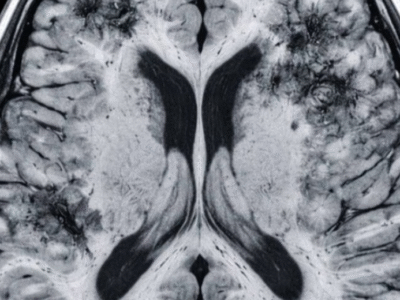

A principal conexão encontrada pelos pesquisadores é a redução nos níveis circulantes de testosterona das usuárias, considerada crucial para o desejo sexual. No entanto, essa diminuição da libido não é mencionada nas bulas das pílulas, e muitos médicos não estão cientes desse possível efeito colateral.

A pílula anticoncepcional combinada reduz os níveis de testosterona de duas maneiras: suprimindo a produção e aumentando a produção de uma proteína que inativa a testosterona. Esse declínio na testosterona livre é considerado uma causa potencial da diminuição da libido, além de afetar a lubrificação e, em casos mais graves, causar vestibulodinia.